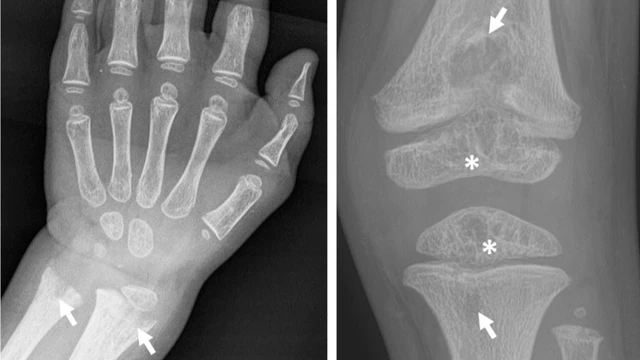

Các chỉ số khối lượng xương kiểm tra sức khỏe xương trong cơ thể trong việc đánh giá sức khỏe xương, nhất là trong việc chẩn đoán loãng xương (osteoporosis) hoặc theo dõi tình trạng sức khỏe xương. Đo lường khối lượng xương thường được thực hiện thông qua các phương pháp như quét DEXA hoặc x-ray để xác định mật độ xương và đánh giá tình trạng xương.